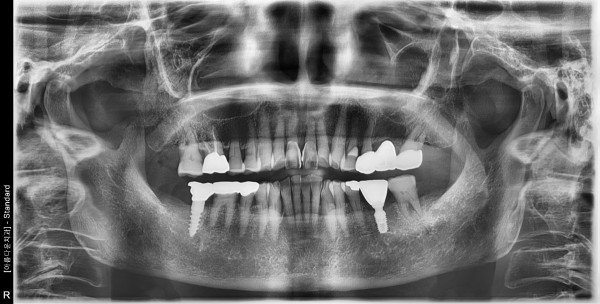

86세 여자 하악좌측 구치부 뼈이식및임플란트식립